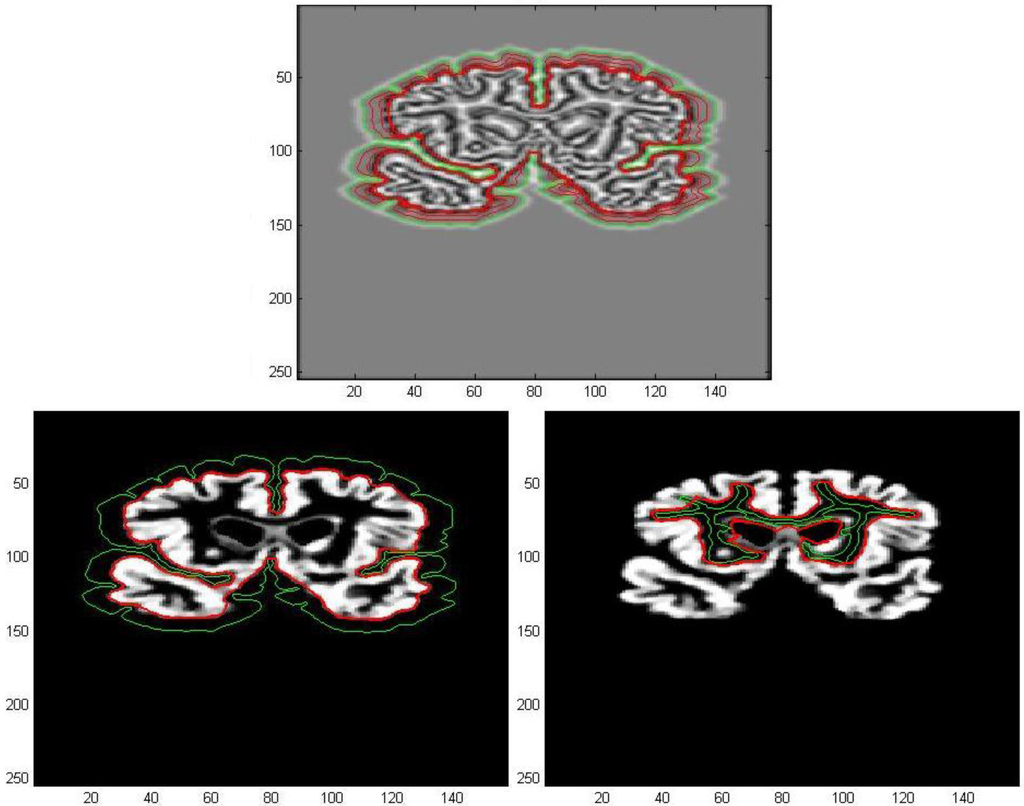

The first processed GM image (Figure 11) refers to a subject of the control group (see the first image of Figure 12). The force field has been evaluated from Equation (9) after eight iterations, the overlapping green curves represent initial contours that are automatically selected from the contour map of divergence. In Figure 13 and Figure 14 we have treated GM images derived from two patients affected by Alzheimer’s disease and they refer respectively to the second and third images which are shown in Figure 12. Once edges are detected, we produce a boundary representation of gray matter that can be used for an automatic analysis of shapes from the geometrical, metrical or morphological point of view.

Figure 14. Edge extraction with AVF force field after 8 iterations.

Algorithms 05 00636 g014